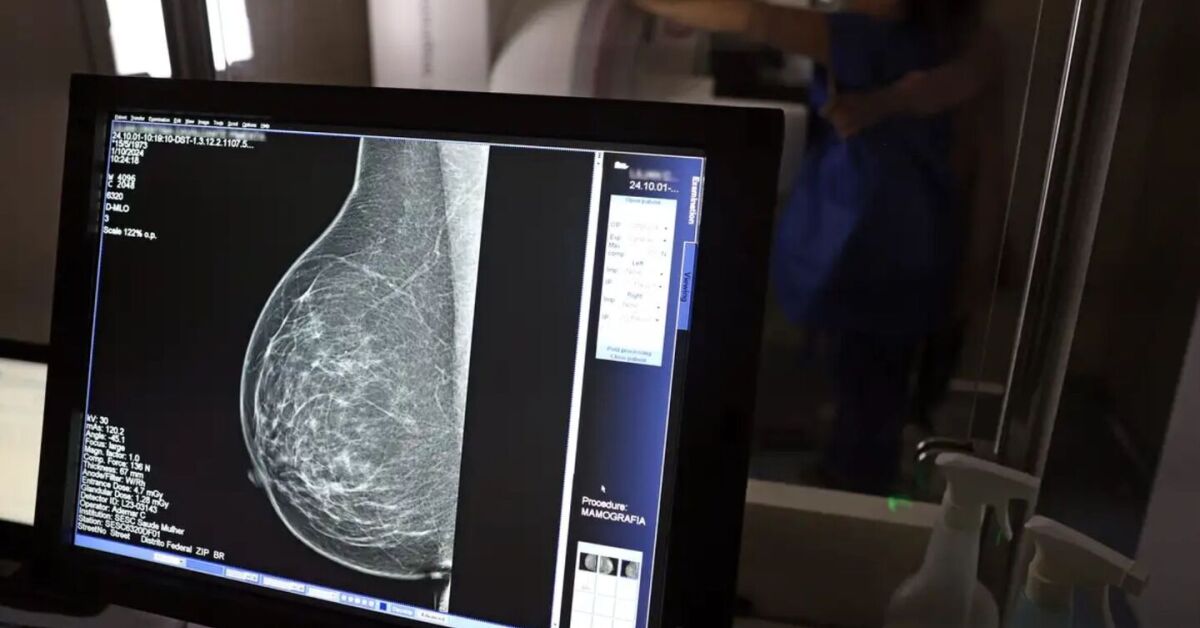

Exame de mama pelo SUS.

Exame de mama pelo SUS. Foto: José Cruz/Agência Brasil

Em junho deste ano, 77.243 brasileiras aguardavam por uma mamografia no Sistema Único de Saúde (SUS). Santa Catarina é o estado com mais mulheres na fila de espera, cerca de 17 mil.  Em seguida, aparecem São Paulo (15 mil) e Rio de Janeiro (12,5 mil). Juntos, os três estados somam 56% do total de pacientes à espera do principal exame para detecção do câncer de mama. Os dados foram divulgados nesta quinta-feira, 31 de outubro, pelo Colégio Brasileiro de Radiologia e Diagnóstico por Imagem (CBR).

Segundo a entidade, em alguns locais do país, o tempo de espera por uma mamografia na rede pública pode chegar a 80 dias. O exame, quando realizado em tempo hábil, permite a detecção precoce de alterações mamárias, aumentando as chances de tratamento bem-sucedido e reduzindo a necessidade de intervenções invasivas e onerosas.